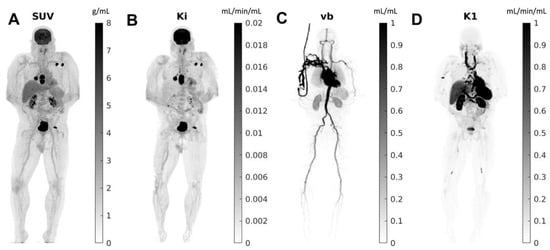

As described earlier, the high sensitivity and dynamic range of total-body PET imaging allow for imaging at much later time points post radiotracer injection (up to 5–6 half times). This is particularly important as tumor contrast typically increases with time, given the clearance of tracer from other tissues. For example, most malignant lesions, including primary cancers and metastatic lesions, would show higher FDG uptake 2 h post-injection rather than 1 h. Thus, delayed imaging can add vital information regarding disease extent by enhancing tumor uptake and detecting smaller or lesser-avid lesions [17,18]. Total-body PET also affords the opportunity to obtain kinetic information using time series scans and kinetic modeling methods (Figure 2) [19]. This kinetic information can then be applied to identify small regions of tumoral infiltration, as some small lesions are below the resolution limit of the scanner and cannot be visualized, but sufficiently alter the kinetics within a voxel [10]. Such a paradigm allows for the delineation of low-grade diseases (cancers, inflammation/infection).

Figure 2.

Total-body parametric images estimated from a 60-min dynamic 18F-FDG scan of a patient with metastatic cancer on the uEXPLORER: (A) SUV; (B) FDG net influx rate (Ki); (C) fractional blood volume (vb); and (D) FDG delivery rate (K1). Reprinted with permission from Ref. [19]. Copyright 2021 Elsevier.